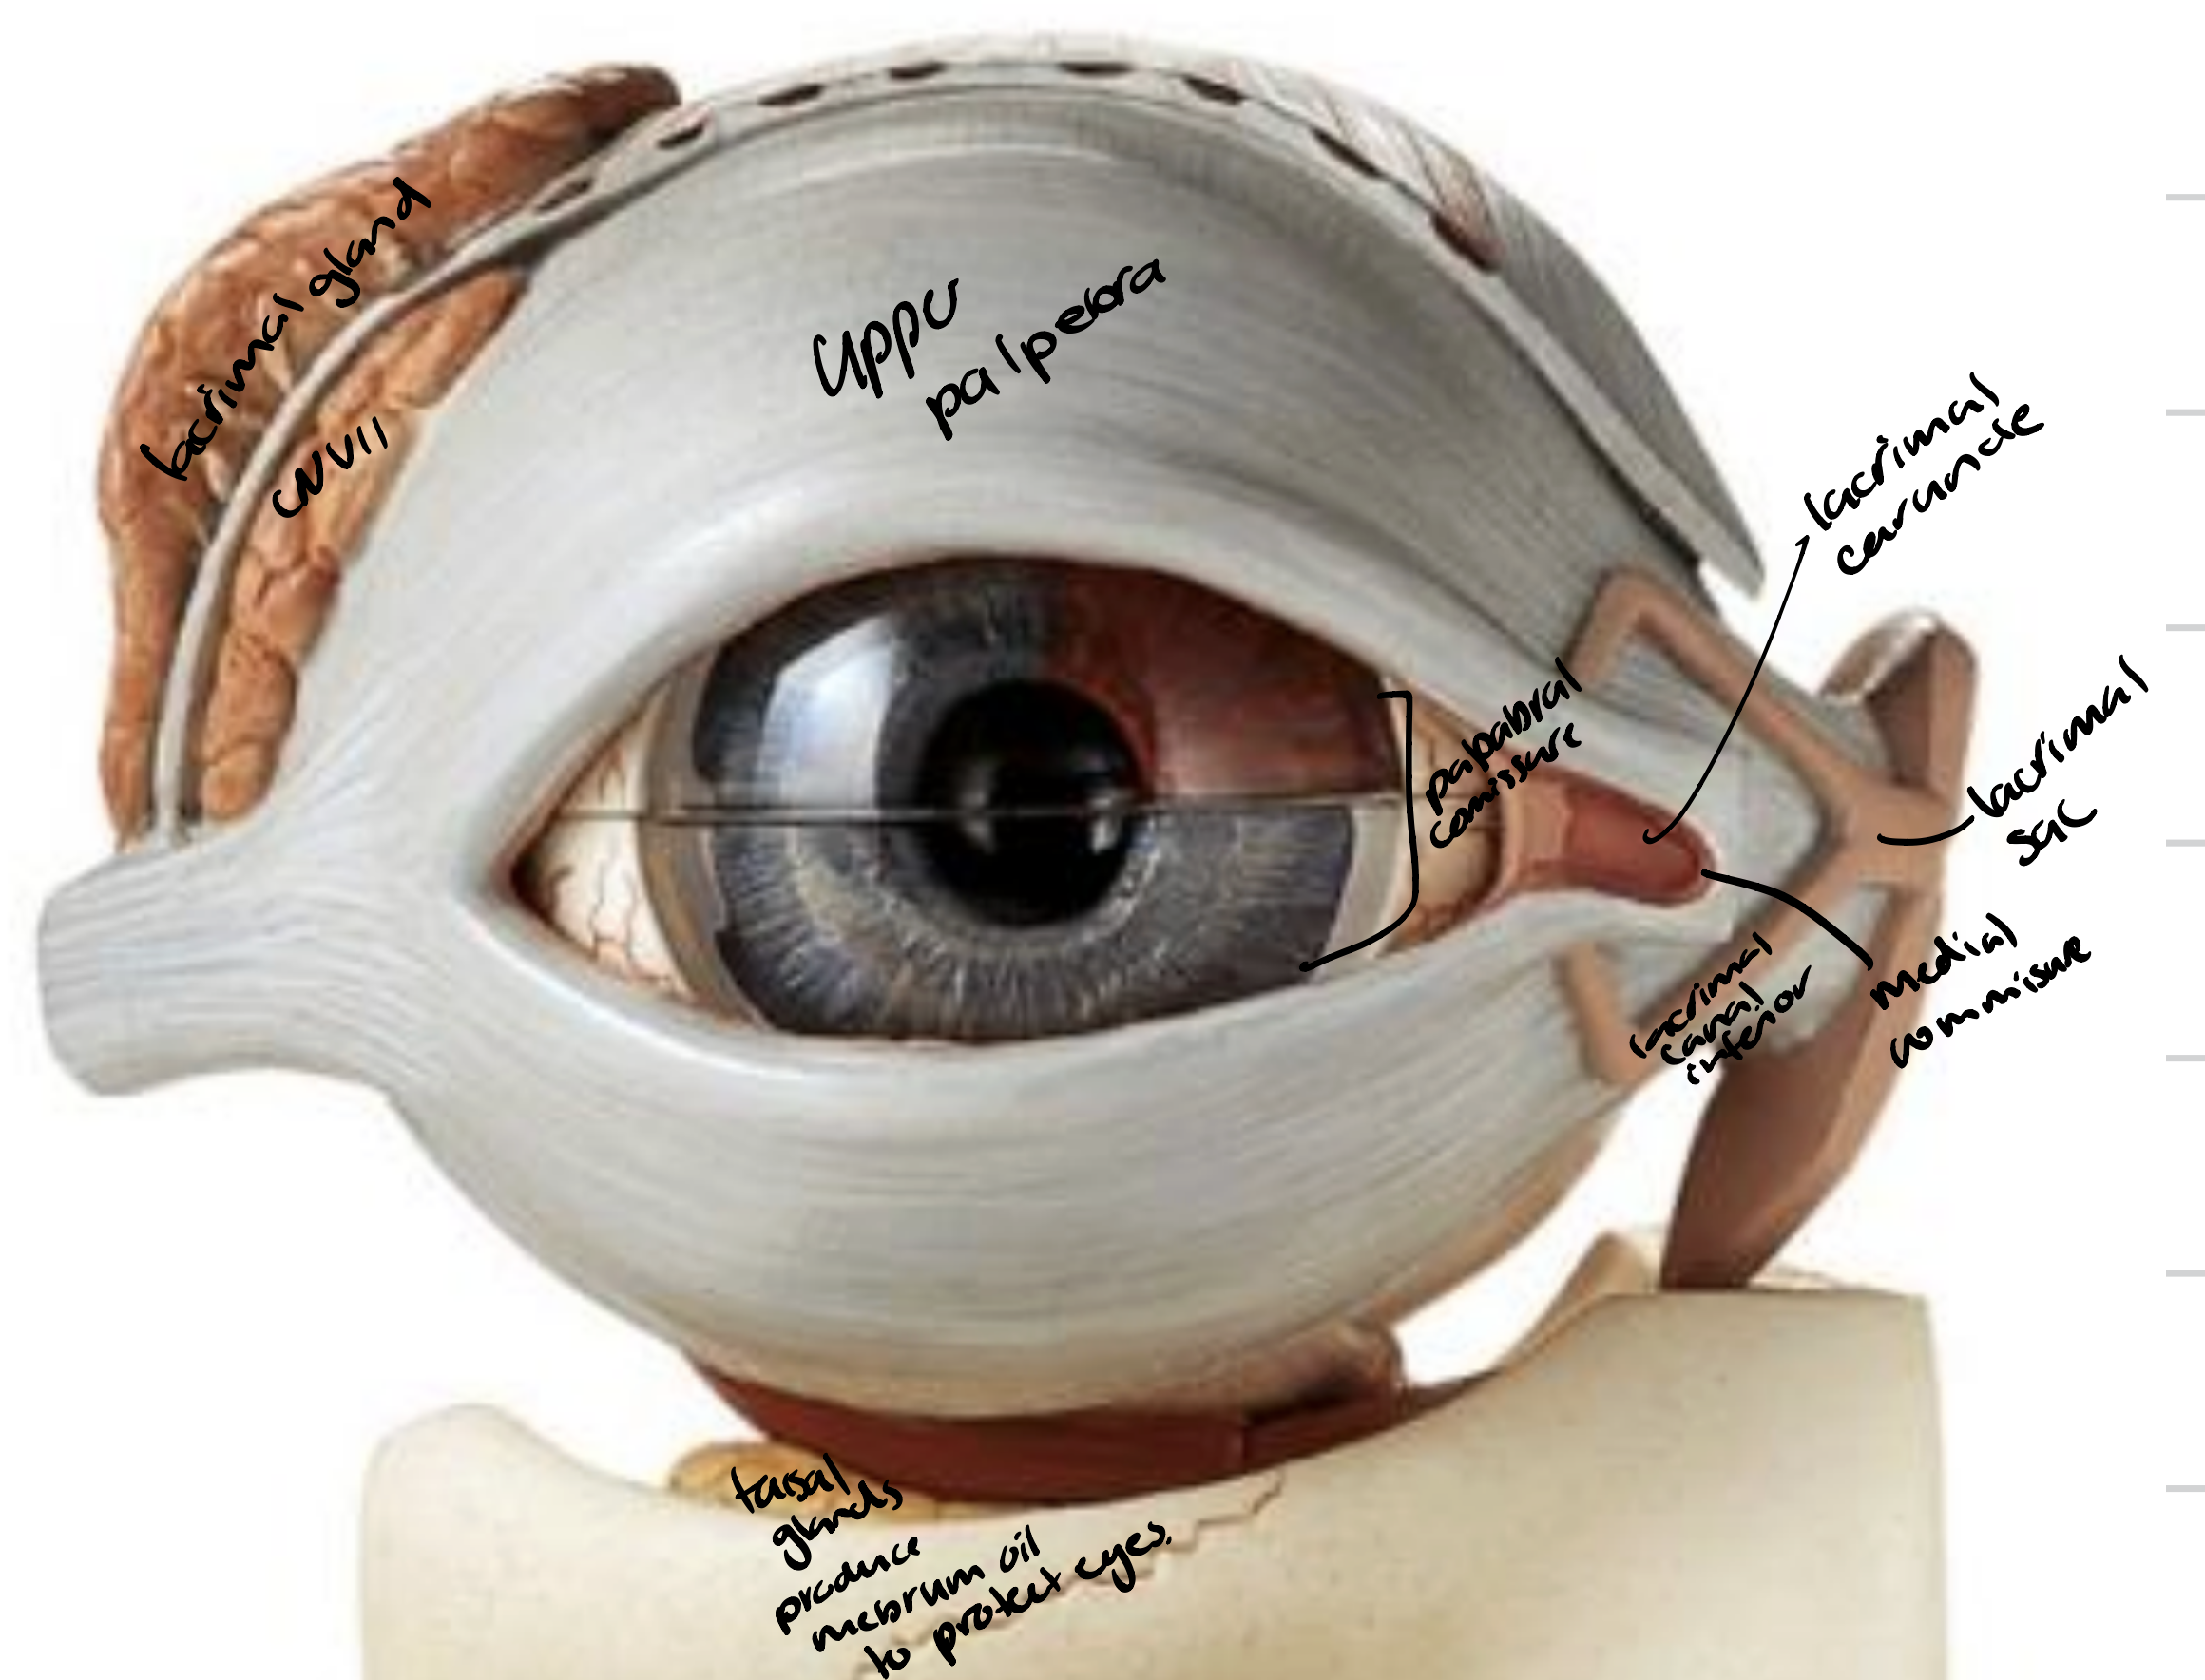

Eye

Upper palpebra

Lacrimal caruncle

Medial commissure

Palpabral fissure

Lacrimal gland

Superior and inferior lacrimal canals

Lacrimal sac